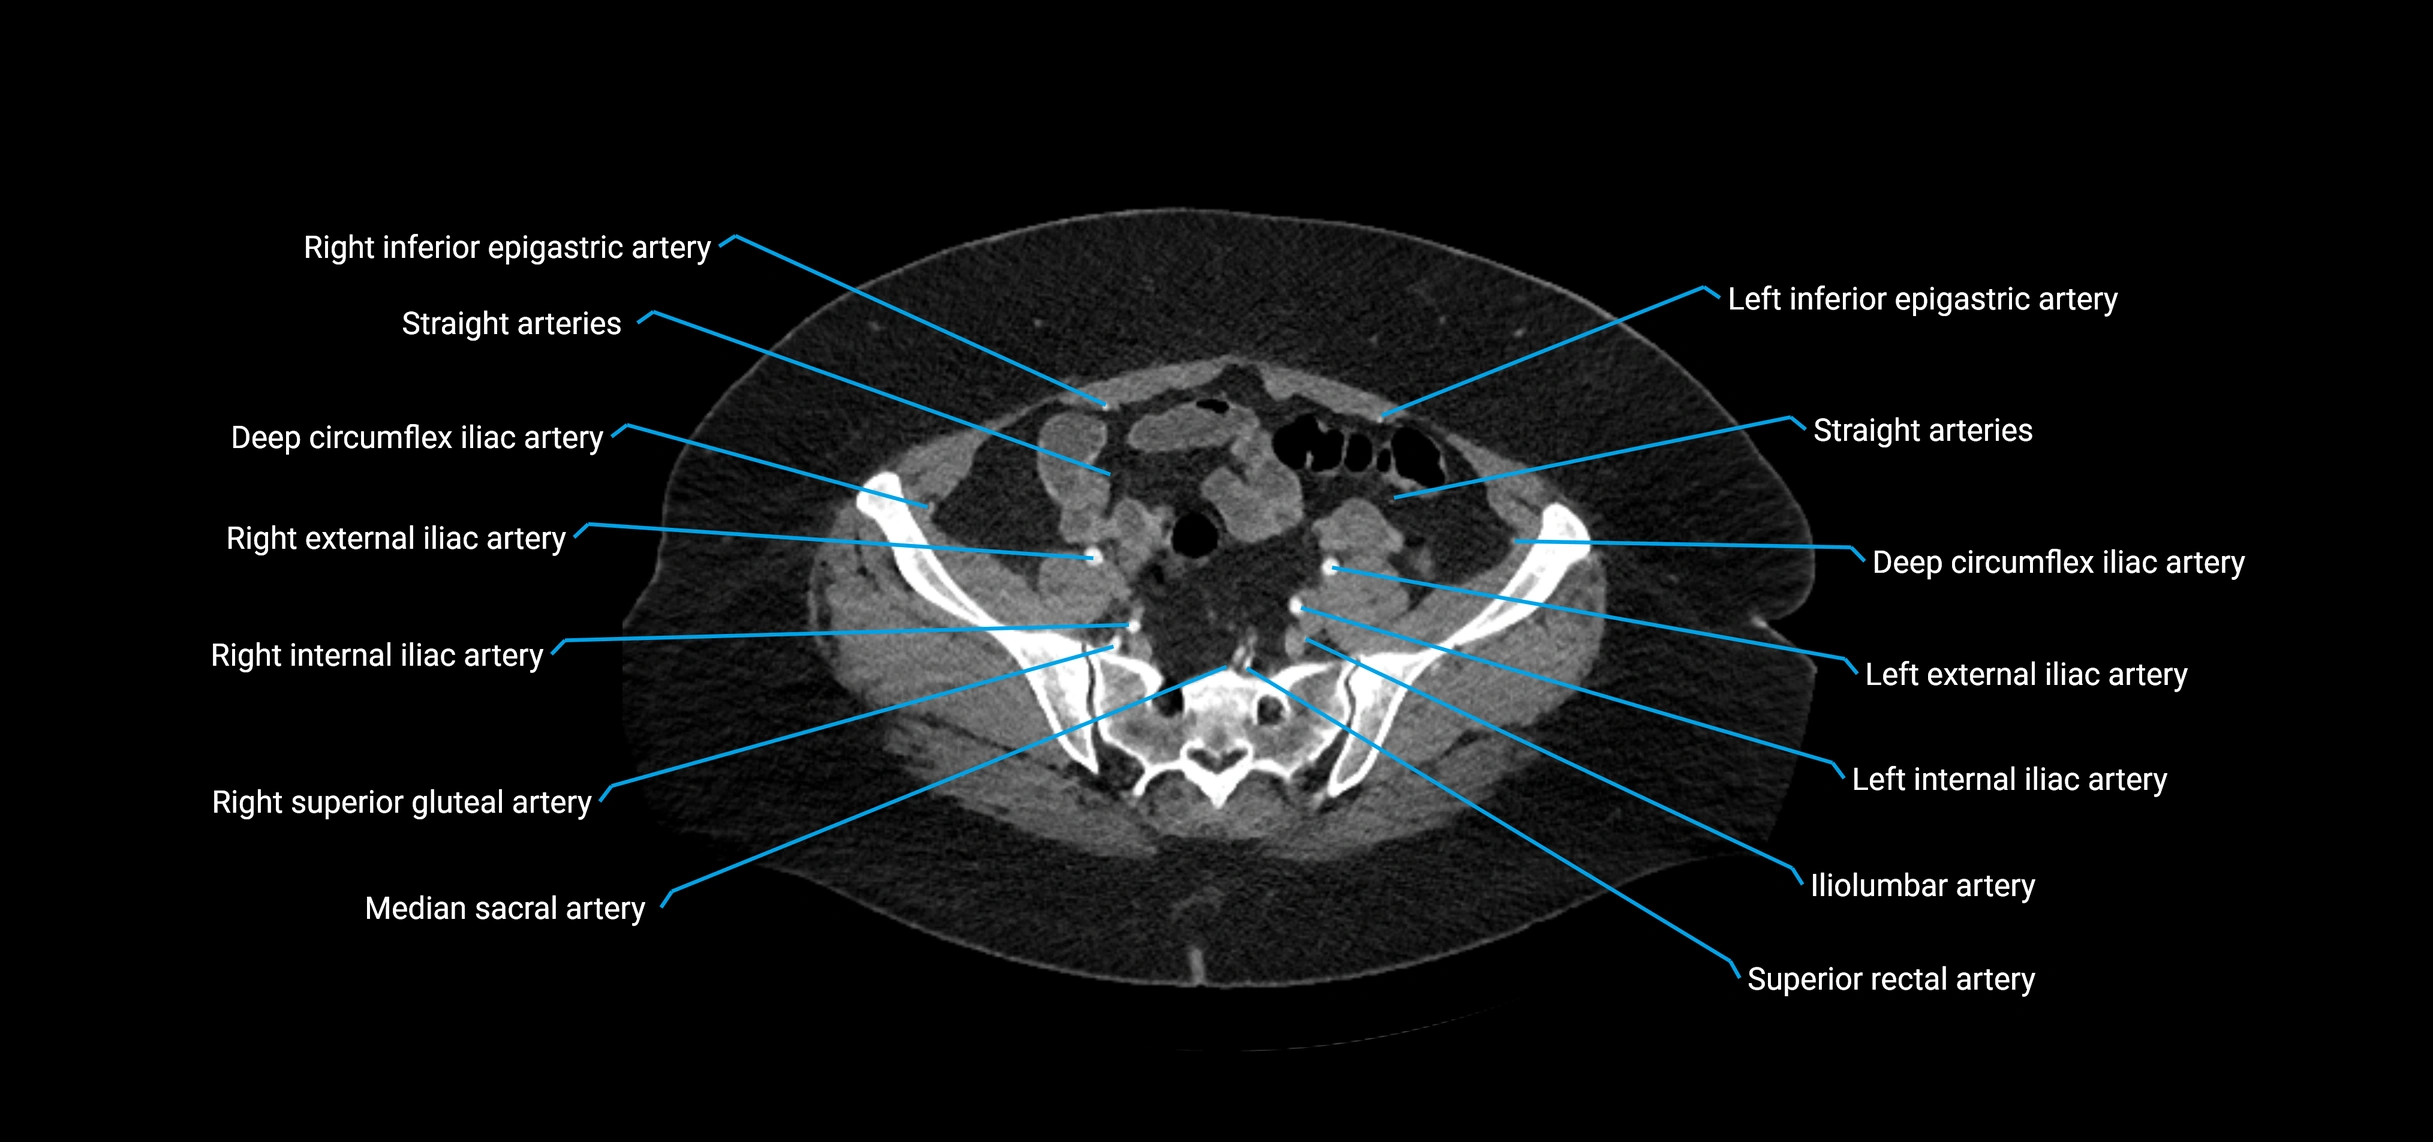

Contrast-enhanced CT (CTA):

• Gold standard for abdominal aortic imaging

• Provides excellent detail of lumen, wall, aneurysm, thrombus, and branch vessels

• Multiplanar and 3D reconstructions help in aneurysm measurement, stent graft planning, and dissection evaluation

• Detects acute rupture, traumatic injury, or occlusion with high sensitivity